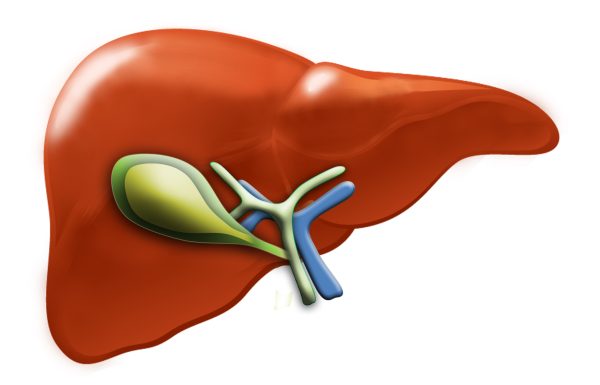

Анатомия и особенности Гартманова кармана желчного пузыря